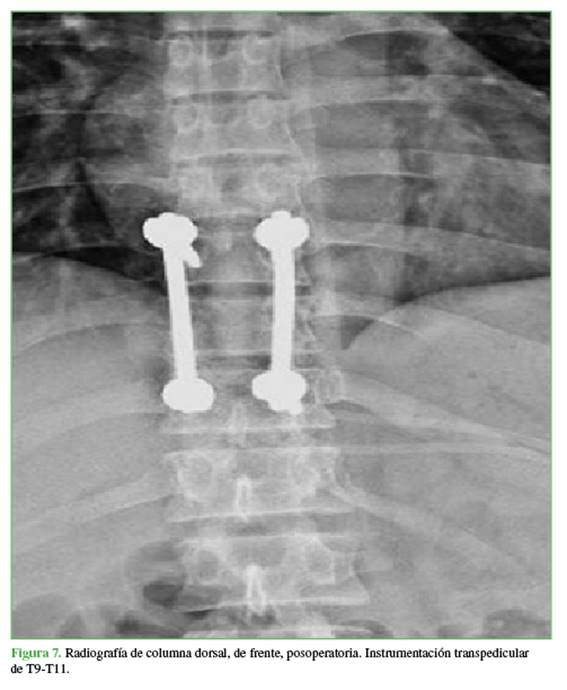

Finalmente, se estabilizó mediante la implantación de barras y tornillos pediculares de T9 a T11 (Figura 7).

Con buena evolución y sin progresión del déficit neurológico, el paciente fue dado de alta a los 4 días. A los 6 meses de la cirugía, el paciente deambula sin limitaciones, y la fuerza muscular ha mejorado, sin progresión del déficit neurológico en el examen de seguimiento clínico.